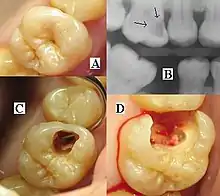

A person experiencing caries may not be aware of the disease.[12] The earliest sign of a new carious lesion is the appearance of a chalky white spot on the surface of the tooth, indicating an area of demineralization of enamel. This is referred to as a white spot lesion, an incipient carious lesion or a "micro-cavity".[13] As the lesion continues to demineralize, it can turn brown but will eventually turn into a cavitation ("cavity"). Before the cavity forms, the process is reversible, but once a cavity forms, the lost tooth structure cannot be regenerated. A lesion that appears dark brown and shiny suggests dental caries were once present but the demineralization process has stopped, leaving a stain. Active decay is lighter in color and dull in appearance.[14]

As the enamel and dentin are destroyed, the cavity becomes more noticeable. The affected areas of the tooth change color and become soft to the touch. Once the decay passes through the enamel, the dentinal tubules, which have passages to the nerve of the tooth, become exposed, resulting in pain that can be transient, temporarily worsening with exposure to heat, cold, or sweet foods and drinks.[15] A tooth weakened by extensive internal decay can sometimes suddenly fracture under normal chewing forces. When the decay has progressed enough to allow the bacteria to overwhelm the pulp tissue in the center of the tooth, a toothache can result and the pain will become more constant. Death of the pulp tissue and infection are common consequences. The tooth will no longer be sensitive to hot or cold but can be very tender to pressure.

The presentation of caries is highly variable. However, the risk factors and stages of development are similar. Initially, it may appear as a small chalky area (smooth surface caries), which may eventually develop into a large cavitation. Sometimes caries may be directly visible. However other methods of detection such as X-rays are used for less visible areas of teeth and to judge the extent of destruction. Lasers for detecting caries allow detection without ionizing radiation and are now used for detection of interproximal decay (between the teeth).

Primary diagnosis involves inspection of all visible tooth surfaces using a good light source, dental mirror and explorer. Dental radiographs (X-rays) may show dental caries before it is otherwise visible, in particular caries between the teeth. Large areas of dental caries are often apparent to the naked eye, but smaller lesions can be difficult to identify. Visual and tactile inspection along with radiographs are employed frequently among dentists, in particular to diagnose pit and fissure caries.[88] Early, uncavitated caries is often diagnosed by blowing air across the suspect surface, which removes moisture and changes the optical properties of the unmineralized enamel.